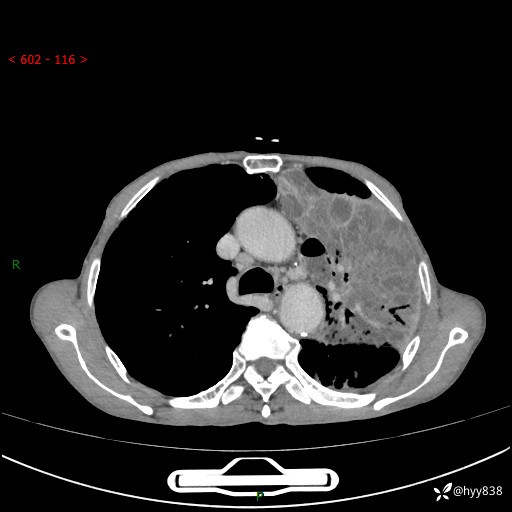

老年男性,反复咳嗽、咳痰、气喘10余年,再发3天。大叶性实变+胸膜病变-结果公布

胸部CT平扫+增强